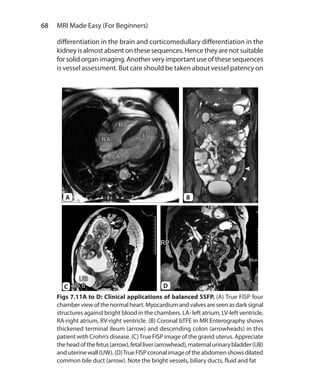

Assistant Professor